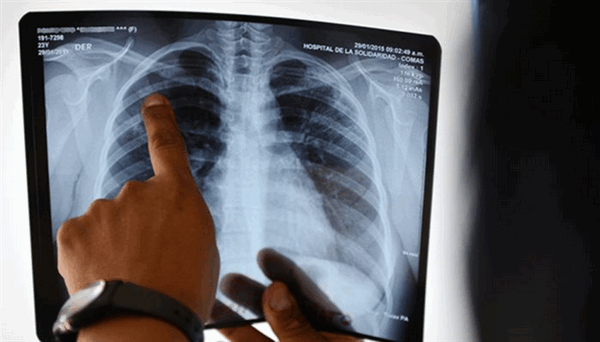

Снимок грудной клетки

Туберкулез - опасное заболевание, которое при несвоевременной диагностике имеет неблагоприятный прогноз. Раннее обследование патологий легких играет важную роль в проведении эффективного лечения. Первым методом, к которому прибегают врачи при подозрении на туберкулез легких или при профилактических осмотрах, является рентгенография.

Первоочередным в дифференциальной диагностике туберкулеза является прохождение флюорографии, пробы Манту, Диаскинтест, бакпосев мокроты на Микобактерии возбудителя заболевания. При сомнительных результатах вышеуказанных обследований, наличии положительных реакций анализов, характерных изменений в составе крови, мочи, мокроты, визуализации патологии в легких на рентгеновском снимке, показана компьютерная или МР-томография легких. Благодаря послойному сканированию интересующей области удается получить детальное изображение органа, обнаружить патологические очаги, определить границы и объем поражения.